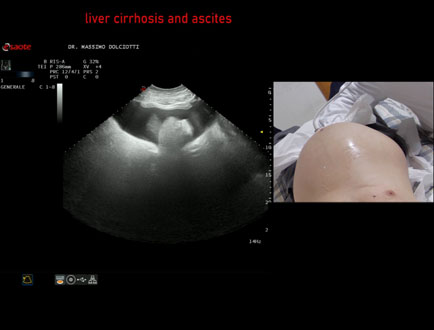

Data inserimento: 08/04/2015

Ecografia del: 27/03/2015

Strumento: Esaote MyLab 50 Gold - Responsabile Linea Cardio Esaote Regione Marche Dr. Franco Fabi

Sonda: Convex Multifrequenza 2,5-6,6 Mhz

Età Paziente: M 69 anni

Motivazione dell'esame: incremento del volume dell'addome, astenia intensa e dispnea. Abuso etilico.

Commento all'esame: le immagini ed il video documentano il fegato ridotto di dimensioni, con profilo irregolare, abbondante ascite, milza normale, rene destro con piccola cisti, pancreas normale.

Conclusioni: cirrosi epatica alcolica scompensata con abbondante ascite (decompensated alcoholic liver cirrhosis with abundant ascites).